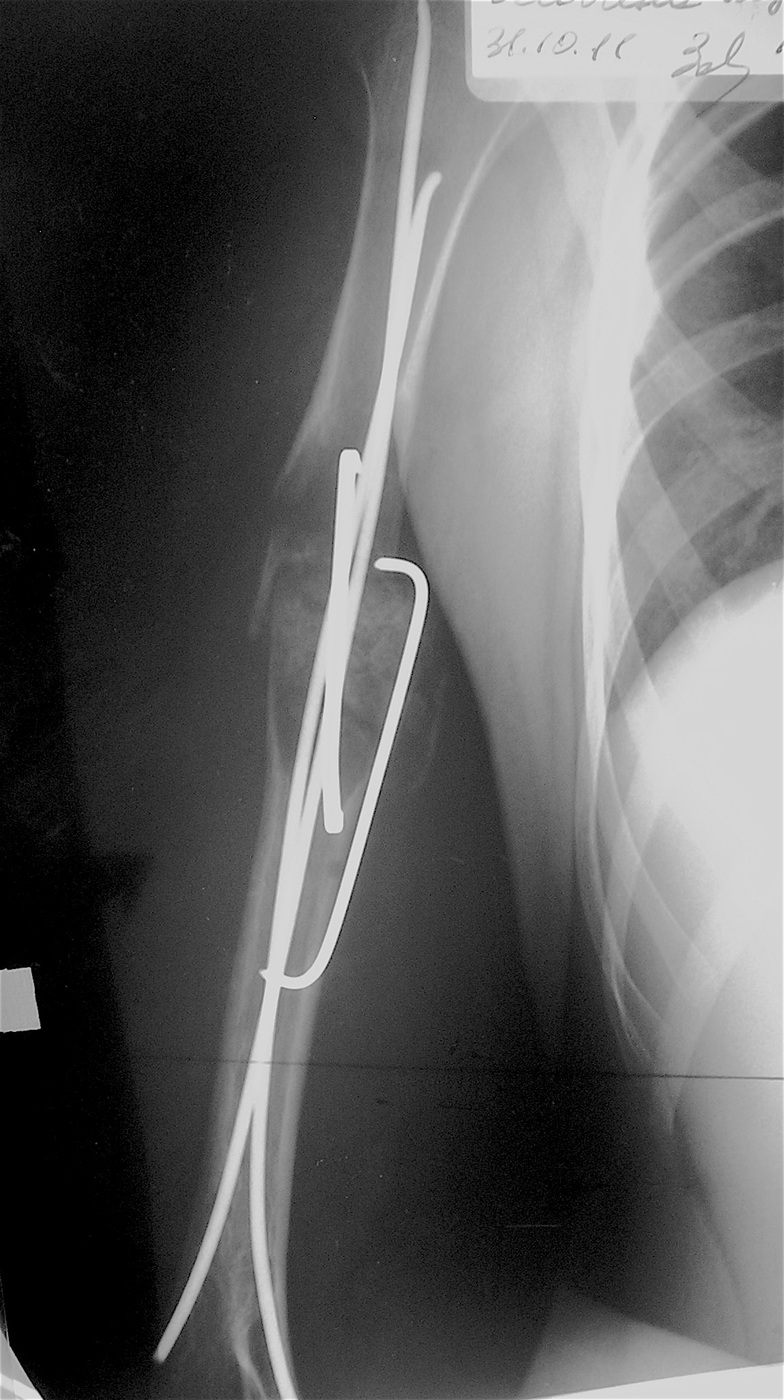

Закрытый, патологический перелом в с/з правой плечевой кости на фоне аневризмальной кисты диафиза правой плечевой кости.

Выполнена операция: экскохлеация кисты, остеосинтез титановыми эластичными стержнями и металлической скобой, аллопластика патологического очага материалом «Лиопласт».